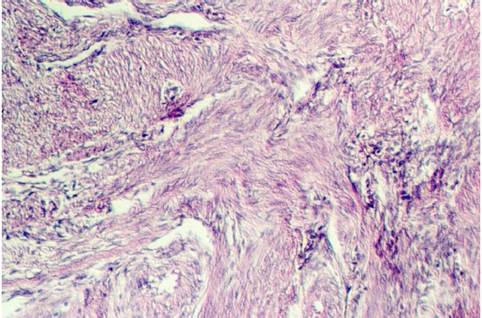

The following photograph illustrates uterine myometrium showing the smooth muscle layers running in interweaving bundles.

Myometrium is responsive to a hormone that is particularly high during labor. What hormone is this and where is it produced and stored?